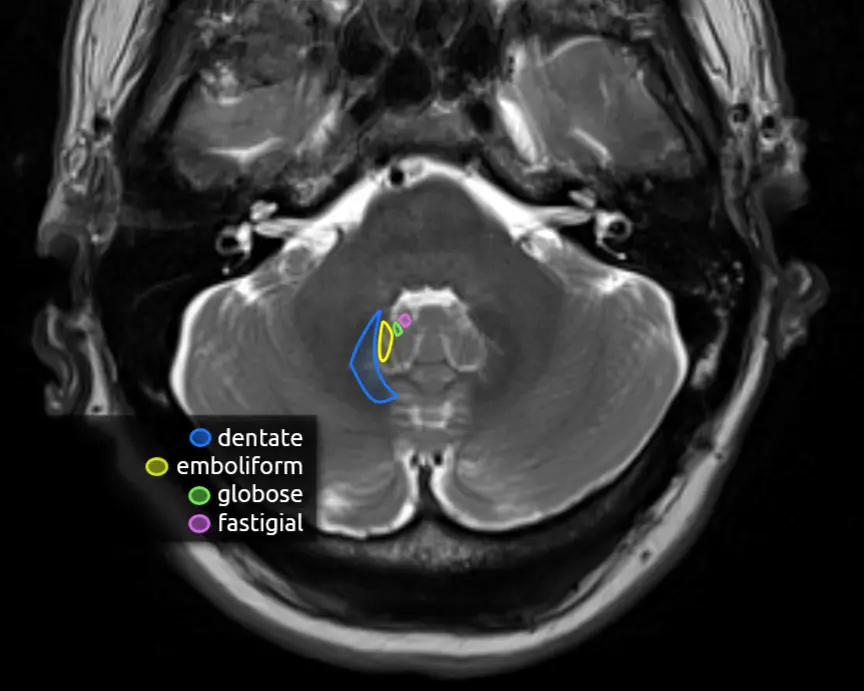

There are four deep cerebellar nuclei that are responsible for all of the signals leaving the cerebellum. The largest, most lateral, and only one that is easily identifiable on routine brain imaging is the dentate nucleus.

Most fibers from the deep cerebellar nuclei go through the superior cerebellar peduncle, cross in the midbrain (decussation of the superior cerebellar peduncles), and synapse on neurons in the ventral lateral (VL) nucleus of the thalamus. Some fibers from the dentate, emboliform, and globose nuclei go to the red nucleus. The fastigial nucleus also sends fibers to the tectum.

Dentate nucleus: motor planning, fine motor movements, cognition.

Interposed nuclei (emboliform + globose): limb movements and stability.

Fastigial nucleus: truncal movements, vestibular functions.